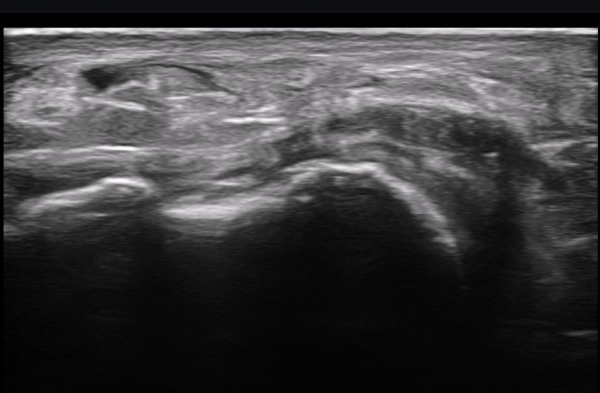

ºñº¹½Å°æ Á¾´Ü¸é°Ë»ç(»çÁø 14, 15)¿¡¼­ ºñº¹½Å°æÀÇ Àü¹ÝÀûÀÎ Àú¿¡ÄÚ ºÎÁ¾°ú ºñº¹½Å°æ ½ÉÃþÀ¸·Î ´Üºñ°ñ°Ç³»

³¶Á¾¼º º¯º¯ÀÌ °üÂûµÈ´Ù.